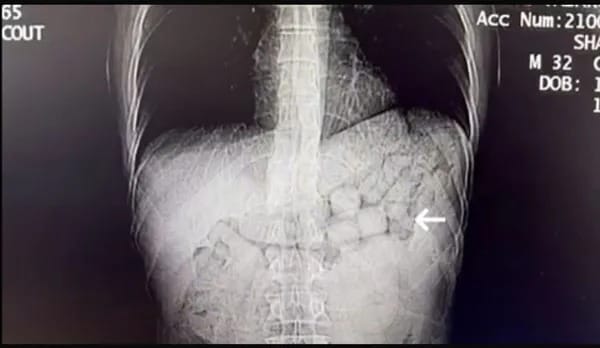

MİDE VE BAĞIRSAKLARINDAN 807 GRAM METAMFETAMİN ÇIKTIŞüphelilerin, tomografi görüntülerinde, mide ve bağırsaklarıda yabancı cisimler bulundu. Yaklaşık 3 gün süren kontrollerin ardından yabancı uyruklu uyuşturucu taciri 2 kişinin mide ve bağırsağından 91 kapsül halinde 807,15 gram Metamfetamin maddesi çıktı.